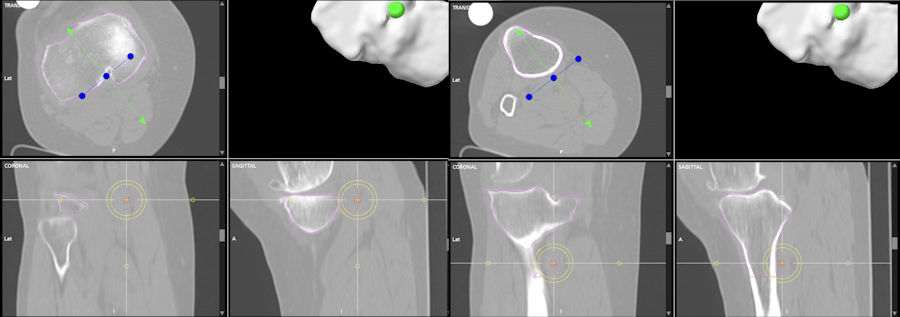

Kişiye özel dizilimin saptanması ve uygulanması için hassas ölçümler ve ayrıntılı bir planlama gereklidir. Standart diz röntgenleri ile bunun yapılması mümkün değildir. Bunun için hastanın ayakta dururken çekilen, kalça, diz ve ayak bileğini tek bir görüntüde içeren röntgen grafileri ile başlanır. Burada özel yazılımlar kullanılarak yapılan hassas ölçümler planlamanın ilk aşamasıdır. Hastanın kalça, diz ayak bileği aksı, diz ekleminin eğimi ölçülür ve hastanın olması gereken dizilim şekline karar verilir. Robotik cerrahi planlamasında kullanılan 3 boyutu bilgisayarlı tomografi (BT) ölçümleri daha da hassas bir ölçüm ve planlamaya izin verecektir (Resim 2).

Bu ölçümler sonrası, ameliyat sırasında protezin parçalarının her kemiğe en uygun nasıl bir açıda yerleştirilmesi gerektiği hesaplanır. Hastaların %15-20’si mekanik dizilime uygundur ve çoğu kişide birkaç derecelik değişimler yapılması gerekir. Aşırı şekil bozukluğu olan veya ciddi kemik kaybı olan hastalarda, mekanik dizilim hala tercih edilen bir seçenektir ve robotik sistemler ile yüksek doğrulukta yapılabilir (Resim 3).

Fonksiyonel dizilimde, hastanın ameliyat öncesi dizilimi ameliyat sırasında güvenli sınırlar içinde getirilirken aynı zamanda bağ dengesi hiçbir gevşetme veya ek kemik kesisi yapmadan hassas bir şekilde ayarlanır. Çok hassas ölçümler gerektiren bu işlem sadece robotik teknolojiler ile yapılabilir. Bütün bacağın bilgisayarlı tomografisi çekildikten sonra hastaya en uygun dizilim cerrah tarafından belirlenerek ameliyat planı robota yüklenir. Burada amaç, protezin kalınlığı kadar kemik çıkartılması ve aşırı kemik kesilerinden kaçınılması, bu sırada hastanın dizlimi ve eklem çizgisi eğiminin korunmasıdır. Robotik cerrahiye başlandıktan sonra, önceden yüklenmiş olan bu plan, hastanın bağ dengesi mükemmel bir şekilde oluşturulacak şekilde tekrar ayarlanır. Bağ dengesini etkileyebilecek olan kemik çıkıntılar temizlendikten sonra robotik sistem ile değişik açılarda dizin iç ve dış yan bağlarının sıkılığı/gevşekliği dijital olarak 0.5mm hassasiyetle ölçülür. Sonrasında, robota yüklenmiş olan plan üzerinde milimetrik açısal değişimler yapılarak hiç bağ gevşetmesi yapılmadan protezin boyutu ve yerleşimi tekrar ayarlanır. Robotik sistem, bu yeni plana göre bağ dengesinin nasıl olacağını daha hiç kemik kesisi yapılmadan cerraha 3 boyutlu simülasyon olarak gösterir. (Resim 4 ve 5).